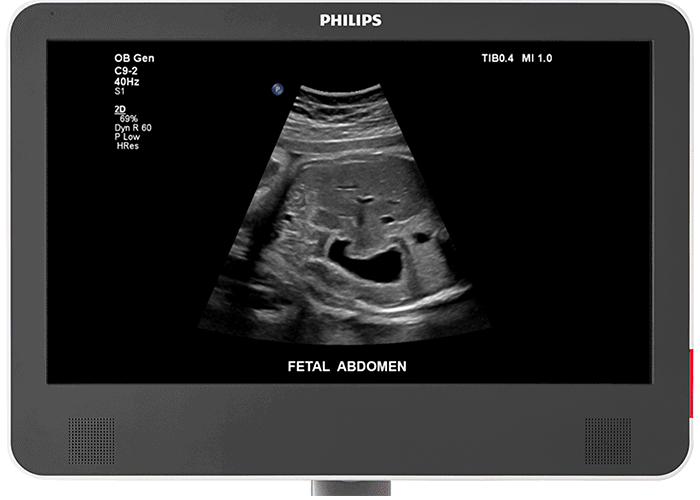

Traductor convex C9-2